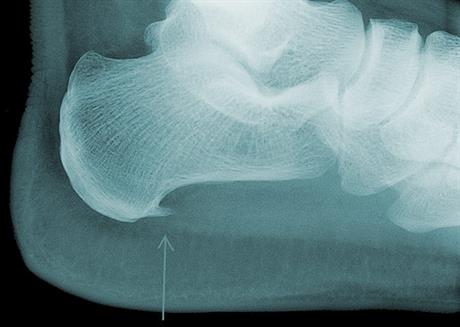

Petni trn

Tijekom posljednjih desetljeća ukupni napori fizioterapije u ovom malom području kreću se u dva smjera- unapređenje postojeće terapije za sam bolni sindrom, te daljnji uvid u moguće uzroke njegova nastanka